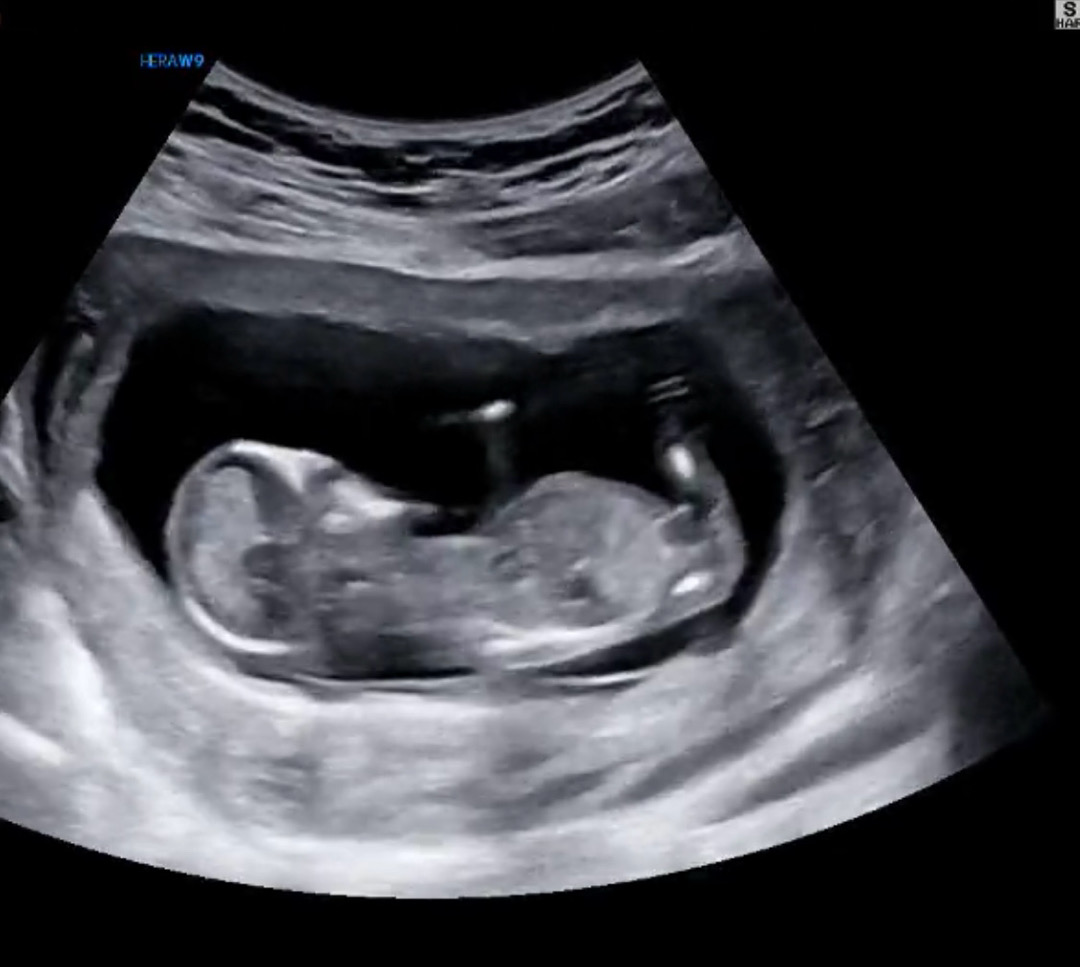

12주 초음파요~! 아들일까요? ㅎ,, 너무 헷갈립니다..

각도법 너무 어려워요 ㅠ 성기 부분이 올라간거 같기도 하고…

저도 살짝 올라가보여서 아들같아보이기도 해요!

딸같은데요.. 쪼금더 지나면 쏙들어갈거같아요~

딸